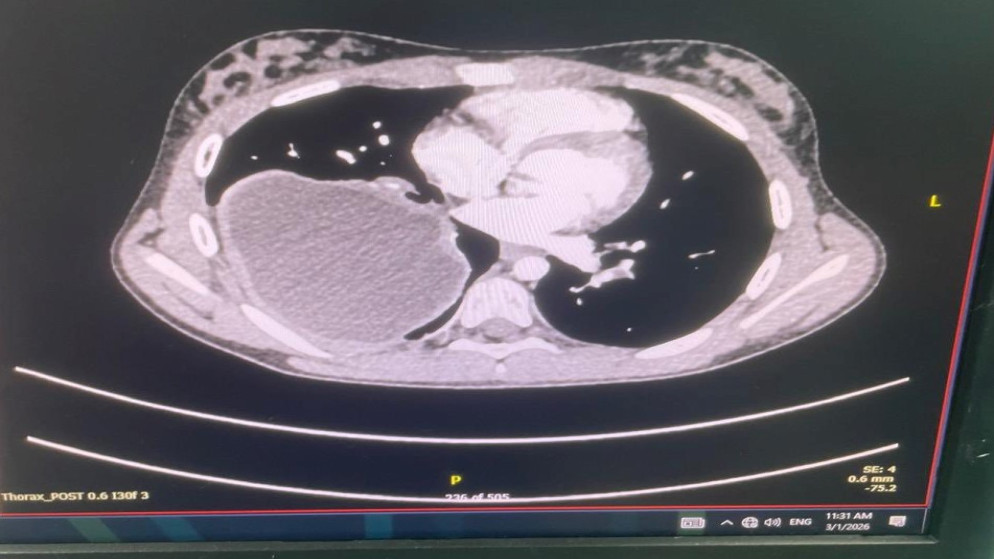

أجرى فريق طبي متخصص بجراحة القلب والأوعية الدموية والأشعة التداخلية، برئاسة العميد الطبيب رازي أبو عنزة عملية نوعية لمريض يعاني من انسلاخ في القوس والشريان الأبهري الهابط وتوسع في الشريان الأبهري الصاعد وارتداد في الصمام الأبهري، وتشوه في الشريان التاجي الأيمن.

وقال مستشار جراحة القلب والأوعية الدموية إن هذه العملية تعدّ من أصعب وأعقد العمليات في مجال جراحة القلب على مستوى العالم، حيث إنها استمرت لمدة 10 ساعات في المرحلة الأولى و3 ساعات في المرحلة الثانية، وفي المرحلة الأولى تم استبدال القوس والشريان الأبهري الصاعد وجزء من الهابط، وإعادة زراعة الشرايين المغذية للدماغ فيما يُعرف بعملية "elephant trunk"، كما تم إصلاح الصمام الأبهري وزراعة الشريان التاجي الأيمن، وفي المرحلة الثانية من العملية التي أُجريت بعد يومين تم زراعة شبكتين في الشريان الأبهري الهابط.

وأضاف أنّ إجراء هذه العملية يحتاج إلى تداخلات كثيرة ومعقدة وتحمل خطورة عالية، خصوصاً في مرحلة تغيير القوس الأبهري، إذ يتم وضع كامل دم المريض خارج الجسم في جهاز القلب والرئة الصناعية، وتبريد حرارة جسم المريض إلى مستويات منخفضة جداً مع المحافظة على تروية دموية مستمرة للدماغ، مشيراً إلى أنه شارك في هذه العملية مستشارا جراحة الأوعية الدموية والأشعة التداخلية العقيد الطبيب محمد الرواشدة والمقدم الطبيب سامر الجفوت، مؤكداً بأن المريض تماثل للشفاء وغادر المستشفى بصحة جيدة.